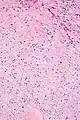

They consist of bland spindle-shaped or stellate-shaped cells in a loose stroma. Renal tubules may be entrapped.

High mag.